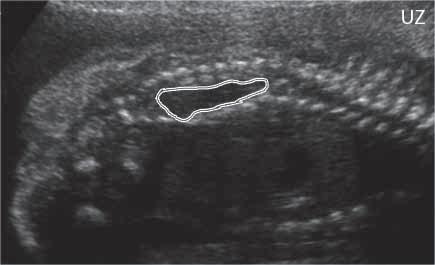

ch

Obr. I.1.7ch Otevřený spinální dysrafismus (defekt bíle označen), prenatální UZ (snímek zapůjčen z archivu prof MUDr P Caldy, CSc )